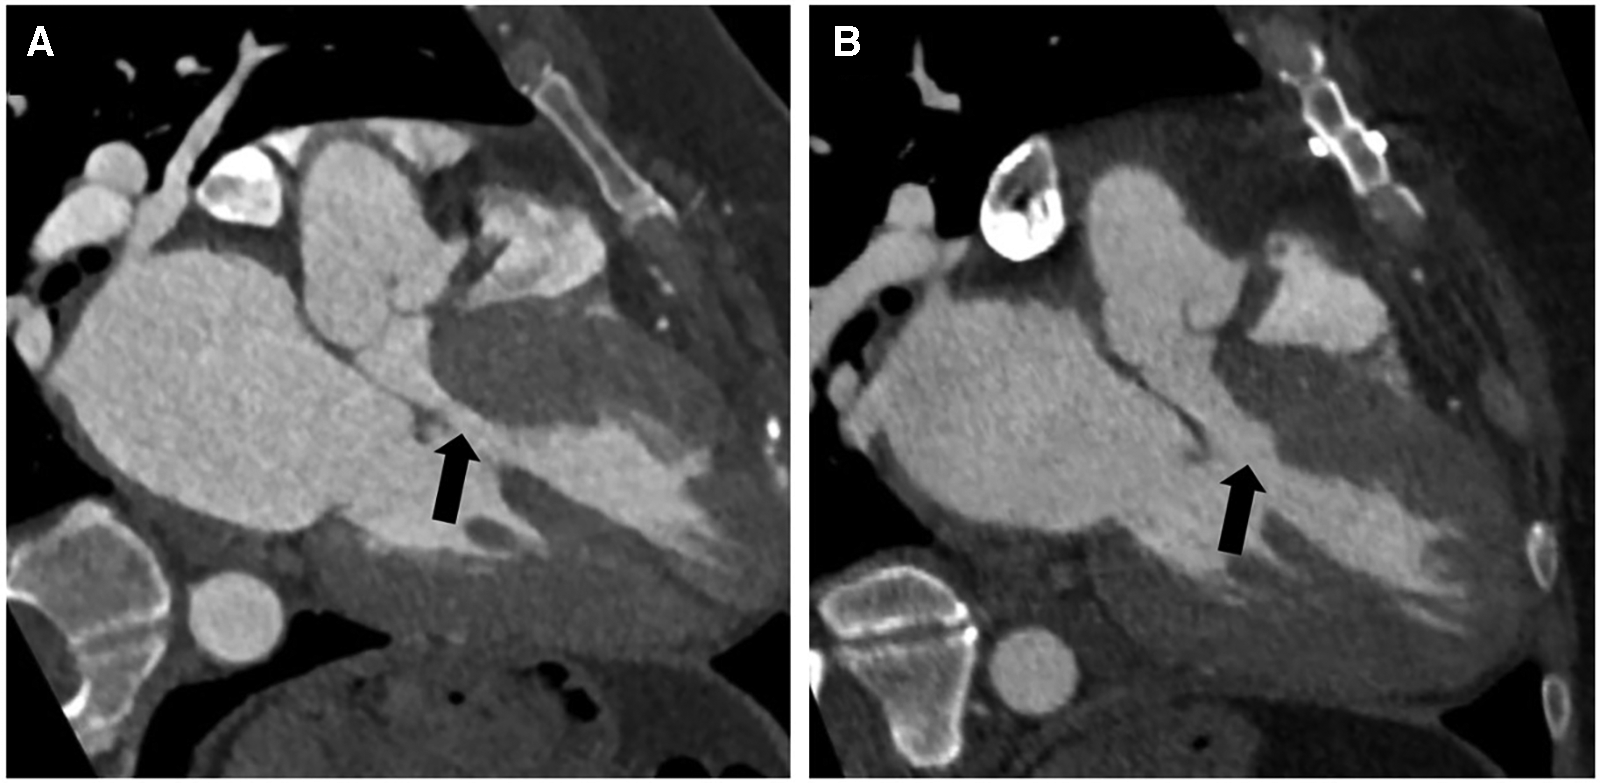

The follow-up was complete, and the mean duration of the follow-up was 8.4 ± 10.3 months. All patients were alive and in NYHA class I. At the last follow-up echocardiography, the mean gradient was 4.4 ± 5.8 mmHg at rest and 9.5 ± 3.3 mmHg after Valsalva. No patient had SAM. There was no coronary-cameral fistula or residual or new flow across the interventricular septum in any patient. No patient required reintervention or reoperation during follow-up (Table 3). Cardiac CECT was performed on two patients for anatomical modeling. As shown in Figure 4, the LVOT is severely obstructed in preoperative CT angiography (Figure 4A). After the septal myectomy using the PlasmaBlade, LVOT is widely open (Figure 4B).

Figure 4

Preoperative contrast-enhanced CT angiography with a three-chamber view during diastole showing asymmetric thickening of the basal septum with narrowing of the left ventricular outflow tract (black arrow) (A). Postoperative contrast-enhanced CT angiography with a three-chamber view shows changes from septal myectomy with significantly reduced narrowing of the left ventricular outflow tract compared to preoperative (black arrow) (B).

Two patients (6.9%) in our first five patients developed VSD, probably due to our learning curve and aggressive resection of the ventricular septum close to the aortic annulus. As our experience with the technique increased, we had no case of VSD in the subsequent 24 cases. The incidence of iatrogenic VSD in our series was significantly higher (6.9%) compared to the reported literature (0.4%–0.7%) (2, 6) due to the smaller number of patients and our learning curve with this technique. In our experience, this technique is easy to learn with a short and steep learning curve of 8–10 cases. Another surgeon in our institution has been able to perform septal myectomy using the PlasmaBlade after observing and cross-scrubbing for five cases. We believe that the use of the PlasmaBlade in other surgical procedures, e.g., pacemaker pocket creation, axillary artery exposure for Impella 5.5 or intra-aortic balloon pump insertion, and pericardiectomy, may increase the comfort level of the surgeon in using the PlasmaBlade and may shorten his learning curve during septal myectomy (24–26). However, our assertion needs further verification with a greater number of surgeons and a larger number of patients. In our series, all patients had nil or single-digit gradient across the LVOT at rest and after Valsalva, immediately after coming off CPB, and the gradient remained low during the follow-up. Widely patent LVOT in CECT chest done in two patients during the follow-up confirms that resection with the PlasmaBlade is durable and does not incite fibrosis. SAM was relieved in all the patients. This shows that adequate and durable muscle resection can be performed with the help of the PlasmaBlade.